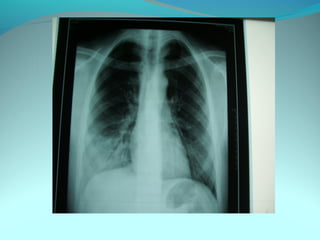

Opacité occupant la partie externe du 1/3 infer du poumon droit

dense et homogene ovalaire de 8cm de grand axe vertical

La limite externe se confend avec une opacité d’environ 1cm comble

les coupole costodiaphragmatique droit

Limitée a sa partie sup par la petit sessure qui est epaisse et pas de

lyse costale

 DIAGNOSTIC :DIAGNOSTIC :

 1_1_cancer bronchique droit( d epaississement)

 2_2_ kyste hydatique au stade sain